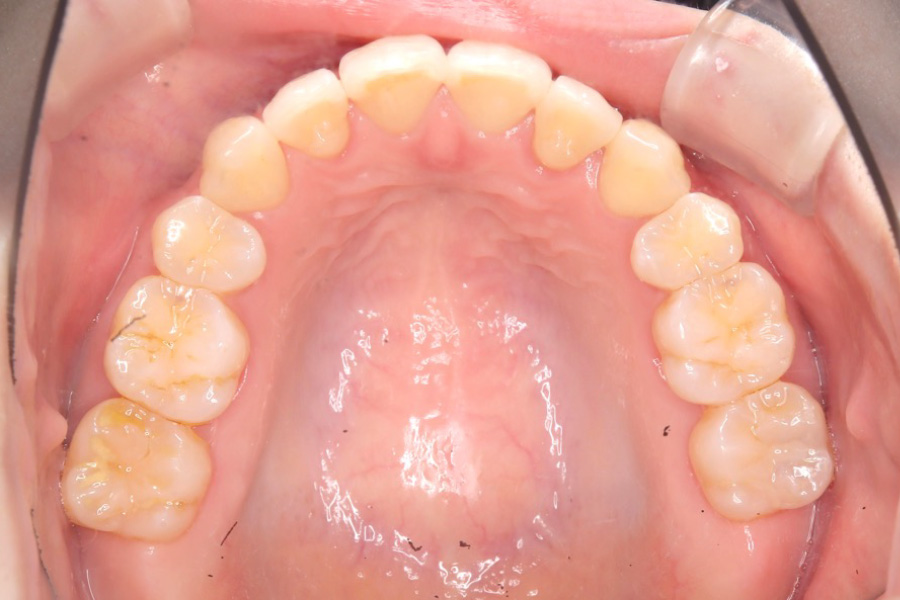

【20代女性】

全体のガタつきを

インビザライン矯正で治療したケース

治療後

主訴 全体のガタつきが気になる

治療内容 インビザライン矯正

小臼歯抜歯